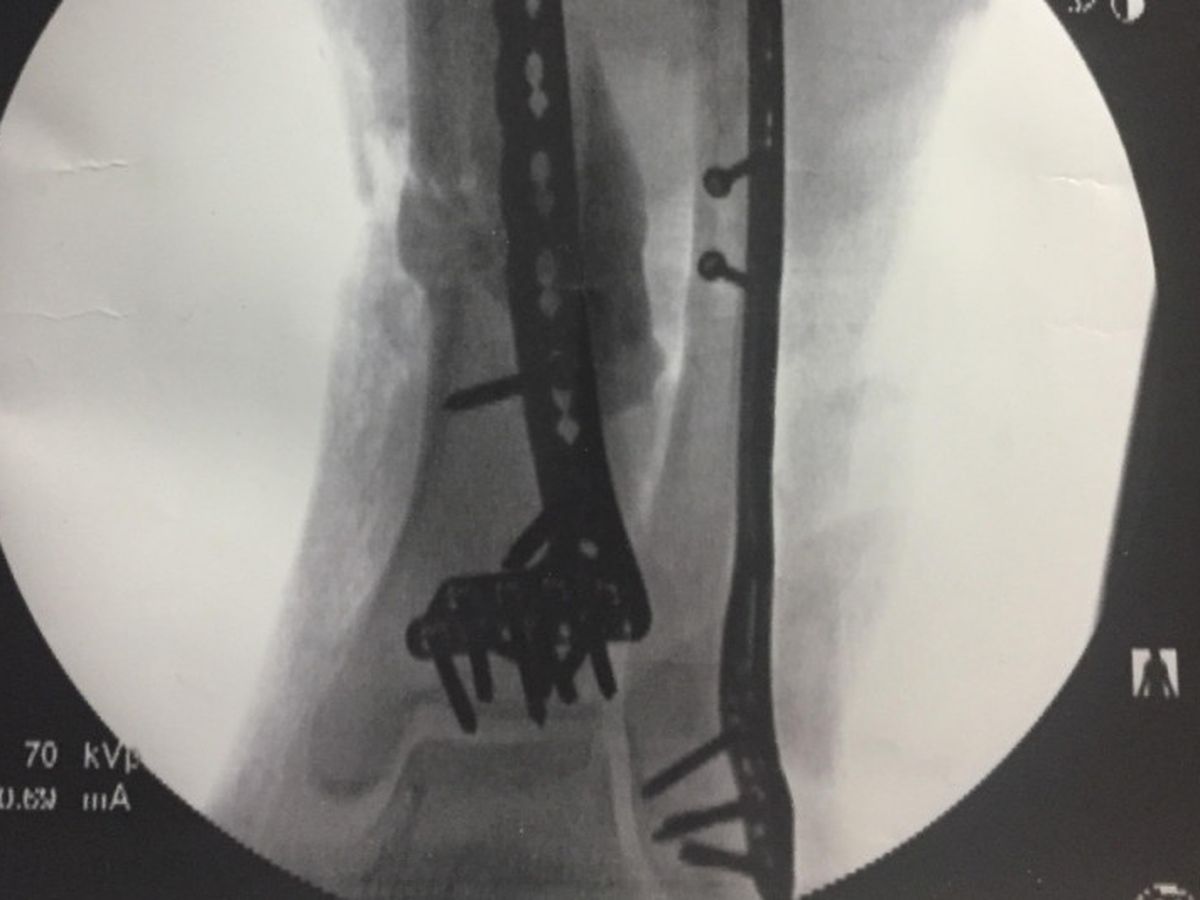

On Friday Sept 8th my brother Bear was on his way to meet some friends to get ready for for a weekend motorcycle trip to the Mackinac Bridge. On the way there a lady was coming down the wrong side of the road and Bear had to lay the bike down. She road up on the bike and then in a moment of panic after hitting him she backed up and dragged Bear and the bike for about two feet before the vehicle came back off the bike at which point the front end came down on Bears leg and blew his calf out. Luckily this happened next to a doctors office and the medical staff there rushed out and got a tourniquet on his leg and kept him from bleeding out until the EMTs arrived. He was taken to Holland Hospital via ambulance where they decided it was best to send him to Butterworth Hospital in Grand Rapids. He was in surgery for about four hours on Saturday the 9th where they discovered the damage was more severe than they thought. His calf muscle was split in two and not repairable via surgery and will have to heal on it's own, His Fibula had a clean break but the Tibia was smashed up pretty bad and there was a chunk of bone that came out and wasn't repairable so he will have to have a bone graft to replace it in 6-8 weeks. His ACL is intact and there was no nerve damage. Bears leg is being held together with some metal rods and screws right now and will be basically couch bound for the next few months and unable to work.